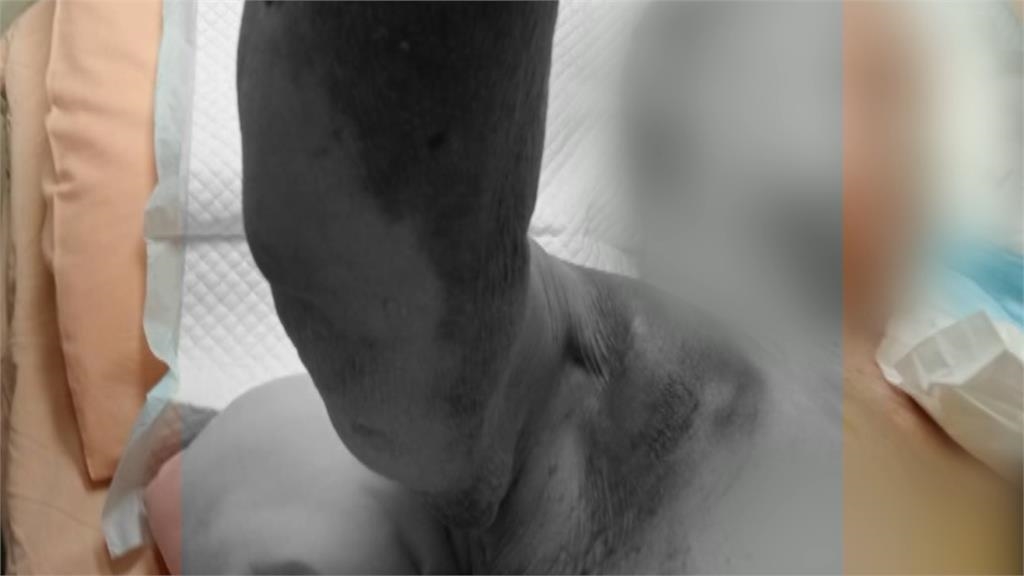

94歲的老母親,坐在輪椅上,表情有些痛苦,仔細一看,竟發現身體莫名出現大面積瘀青,家屬無法理解,母親的傷,到底哪裡來的?女兒驚見媽媽手臂,腹部,大腿等部位都出現瘀青,心中既傷心又難過,詢問護理之家,卻得到這樣的答案。